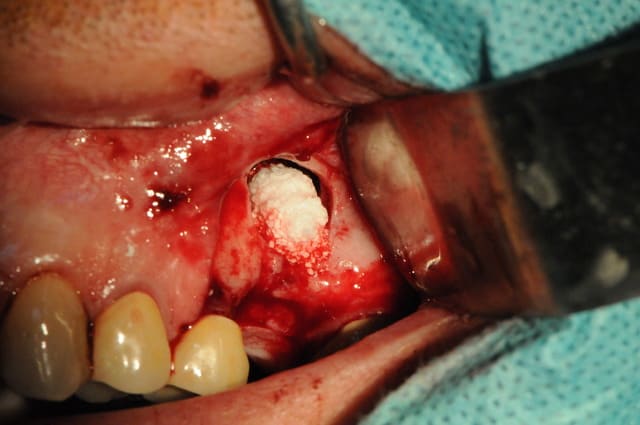

La première fois ne fût pas agréable, parce qu'il s'agit de mon premier implant perdu!

Le deuxième dépucelage concerne mon premier SINUS LIFT.

Hormis le fait que mon insert mectron se soit cassé pendant l'intervention, tous le reste s'est plutôt bien passé.

J'ai terminé avec la boule diamantée.

Beau travail dentiste 57. Je ne compte pas commenter l'indication du sinus-lift mais plutot la chirurgie en elle même.

Tu t'en es très bien sorti pour ton premier. Et tu as pu aussi voir que cela n'est rien de vraiment sorcier contrairement à ce que beaucoup semble dire !

J'ai cependant quelques remarques et certainement quelques conseils pour tes prochains sinus-lift :

- position de la fenêtre latérale : il est pratique de mesurer sur l'OPG ou le scanner la hauteur de crête et de reporter cette mesure in situ, cela t'éviteras de taper dans la corticale et d'avoir un accès décalé et plus génant. Dans le cas où la hauteur de crête est très fine 2-3 mm, il est dans tous les cas fortement conseillé de rester à un minimum de 5mm de cette dite crête et ce afin d'éviter un effondrement crestal difficile à régénerer.

- taille de la fenêtre latérale : elle est dans ton cas acceptable même si j'ai l'habitude d'ouvrir un peu plus ... accès et élévation en sont facilités.

- volet osseux : de par ta préparation à la fraise boule il t'était impossible de repositionner le volet osseux en fin de chirugie. La logique voudrait que tu repousses ce volet dans le sinus afin de créer un "pseudo plafond sinusien". A la vue de tes photos il semblerait que tu es tout de même enlevé ce volet. Est ce que je me trompe ? si oui oublies ma question, si non pourquoi ?

- fracture d'insert mectron : quel est la référence de l'insert qui s'est cassé. Sous quel programme s'est il cassé? J'utilise le mectron pratiquement tous les jours. J'ai en 4 ans d'utilisation cassé un seul insert et par ma faute puisque j'ai alors utilisé un programme inadapté à l'insert.

- implantation simultanée : comme amibien le décrit j'aurais également dans ton cas opté pour une mise en place implantaire dans la foulée puisqu'il n'y a aucun doute à la vue de ton OPG qu'une stabilité primaire aurait été obtenue sans problème avec un implant conique.

- membrane de recouvrement : comme je l'ai écrit dans une autre post, plusieurs review de qualité s'accordent à dire que la recouvrement de la fenêtre d'accés est en corrélation avec un taux de survie implantaire amélioré à long terme. Je n'ai donc rien à te reprocher à ce niveua là. Cependant, j'aurais dans ton cas deplacé mon incision de décharge en mésial de la 25 afin d'éviter d'avoir ma limite membranaire en dessous de mon trait d'incision. Cela évite des complications d'éventuelle exposition si un point lache.